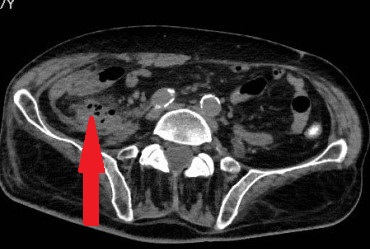

Κόκκινα βέλη. Παχυσμένο τοίχωμα ορθού. Πράσινο βέλος. Περιτονία του μυός ανελκτήρα του πρωκτού (Ευγενική παραχώρηση Dr. V. Penopoulos)